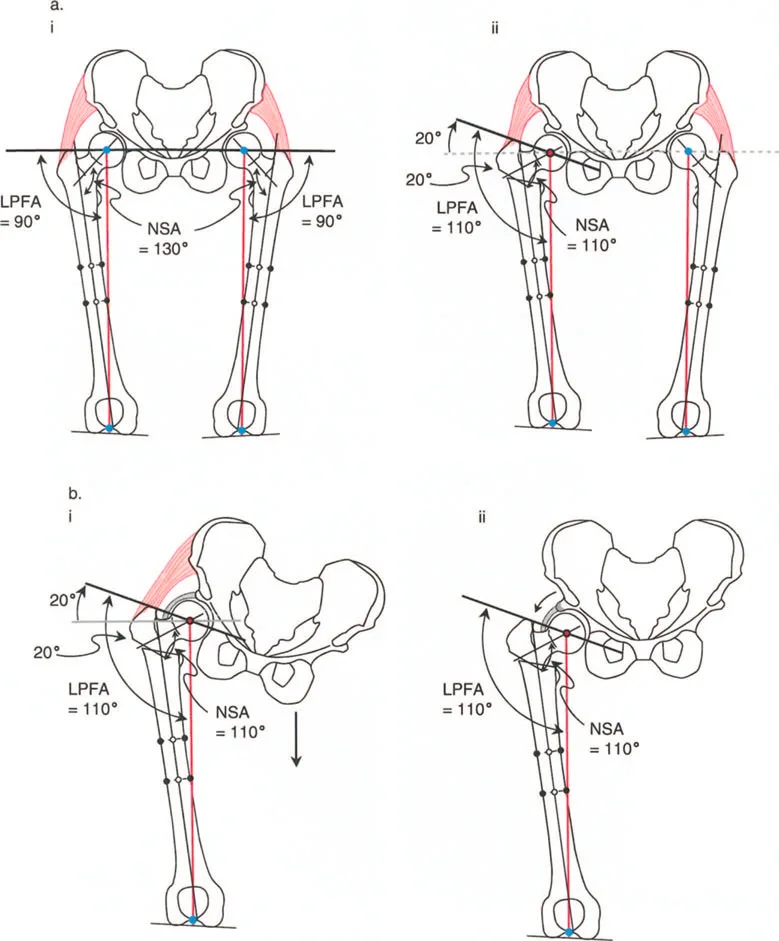

يستخدم جراحو العظام عدة زوايا لقياس محاذاة مفصل الورك وعظم الفخذ، وهي حاسمة في تشخيص التشوهات وتخطيط العلاج:

- الزاوية بين عنق وجسم الفخذ (Neck-Shaft Angle - NSA): هي الزاوية بين محور عنق الفخذ ومحور جسم الفخذ.

- الزاوية الطبيعية: تتراوح عادة بين 125° و 135°.

- كسع الورك (Coxa Vara): تحدث عندما تكون هذه الزاوية أقل من الطبيعي (أقل من 120°)، مما يجعل عنق الفخذ أكثر أفقية.

- فحج الورك (Coxa Valga): تحدث عندما تكون هذه الزاوية أكبر من الطبيعي (أكثر من 140°)، مما يجعل عنق الفخذ أكثر عمودية.

- الزاوية الميكانيكية لعظم الفخذ القريب (Mechanical Proximal Femoral Angle - MPFA): تقيس العلاقة بين محور عظم الفخذ ومستوى المدور الكبير.

- الزاوية الجانبية لعظم الفخذ القريب (Lateral Proximal Femoral Angle - LPFA): تقيس ميل الجزء العلوي من عظم الفخذ.

تؤثر هذه الزوايا بشكل مباشر على ميكانيكا مفصل الورك، وخاصة على ذراع الرافعة للعضلات المبعدة للورك. عندما تكون هذه الزوايا غير طبيعية، يزداد الضغط على المفصل، وتضعف العضلات، مما يؤدي إلى الألم والعرج وتآكل المفصل.

- متى يستخدم: يُطبق عادة في حالات كسع الورك (Coxa Vara)، حيث تكون الزاوية بين عنق وجسم الفخذ صغيرة جدًا (أقل من 120 درجة)، مما يؤدي إلى قصر في الطرف وتضخم في المدور الكبير.

- الهدف: زيادة الزاوية بين عنق وجسم الفخذ إلى المعدل الطبيعي (125-135 درجة)، مما يطيل الطرف ويخفض المدور الكبير، ويحسن ذراع الرافعة للعضلات المبعدة للورك.

ب. قطع العظم الفاروسي (Varus Osteotomy)

- متى يستخدم: يُطبق في حالات فحج الورك (Coxa Valga)، حيث تكون الزاوية بين عنق وجسم الفخذ كبيرة جدًا، أو في حالات التهاب المفاصل التنكسي (الخشونة) لتحويل مناطق تحمل الوزن في المفصل، أو عندما يكون رأس الفخذ بيضاوي الشكل.

- الهدف: تقليل الزاوية بين عنق وجسم الفخذ، مما يزيد من ذراع الرافعة للعضلات المبعدة ويقلل الضغط على المفصل. قد يؤدي هذا إلى إزاحة المدور الكبير للأعلى، مما يستدعي إجراء نقل للمدور الكبير لتعويض هذا التأثير.

- الورك الفاروسي مع المدور الكبير المتضخم: في هذه الحالات، يكون التشوه ناتجًا جزئيًا عن عنق الفخذ وجزئيًا عن تضخم المدور. يتطلب التصحيح الجراحي عادةً قطع عظم فحجي (Valgus Osteotomy) مع نقل للمدور الكبير.

- تشوه فحجي مع دوران داخلي لعظم الفخذ القريب وخلع جزئي للورك: قد يتطلب هذا قطع عظم فاروسي مع إزاحة وسطية ونقل المدور الكبير للأسفل والجانب.